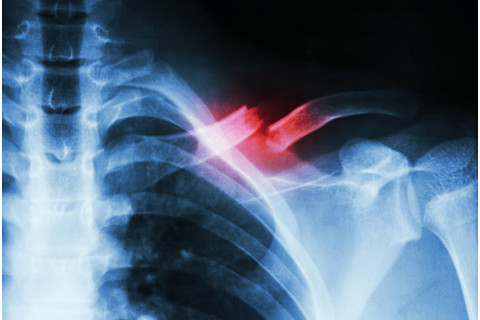

To test the effects of young blood, scientists surgically linked the circulatory systems of young mice and old mice together through a procedure known as parabiosis. They also paired mice of the same age together as a control. Then they fractured the shinbones of both mice once they were paired, to observe the way they healed. Fractured bones healed faster and more effectively in old mice paired with younger mice than in old mice paired with another old mouse. Conversely, young mice that received old blood had a diminished ability to repair fractures. Scientists noted that older bones contain higher levels of a protein called beta-catenin. This protein seems to encourage bone marrow to manufacture cells that hold bone together, rather than cells that actually produce bone. Beta-catenin levels were much lower in old mouse bones nourished by young blood. Therefore, scientists believe young blood cells must secrete a molecule that regulates beta-catenin levels, letting bones heal better and faster. They published their findings this week in the journal Nature Communications.

Photo credit: Puwadol Jaturawutthichai/Shutterstock